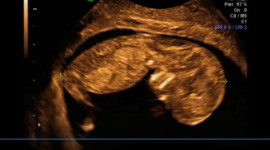

Nad kobietami w ciąży jest szeroko rozpostarty prawny „parasol ochronny”. Poznaj swoje prawa.